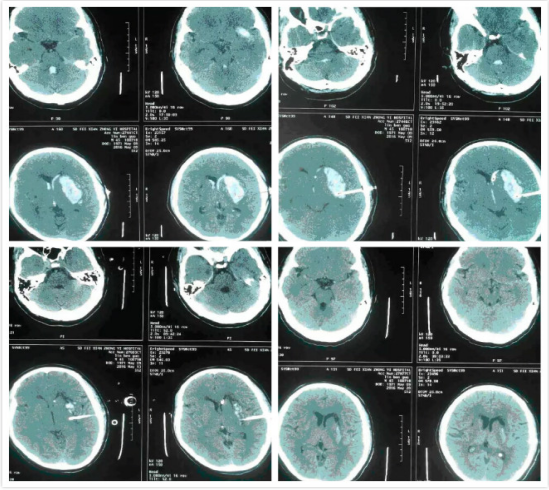

高血壓腦出血術前、術後、術後3天、術後11天CT圖片。